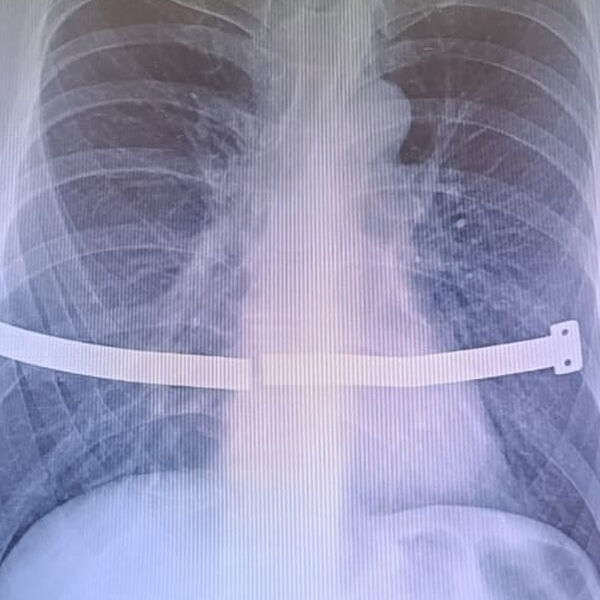

У россиянина разломилась в груди пластина, которую он должен был удалить 13 лет назад

В Сургуте врачи спасли мужчину с разломившейся пластиной в грудной клетке

Врачи Сургутского травматологического центра спасли мужчину, беспечность которого едва не привела к серьезным повреждениям внутренних органов. Случаем из практики поделились в пресс-службе медицинского учреждения.

Пациент 17 лет проходил с металлической пластиной в груди, которая, ожидаемо, раскололась, так как не была предназначена для столь долгой «эксплуатации». Конструкцию установили мужчине для коррекции воронкообразной деформации груди. Устройство следовало удалить спустя четыре года, но пациент не торопился с операцией. В итоге пластина разломилась пополам и один из ее краев стал упираться в оболочку сердца.

Из-за сильных болей пациент обратился к медикам, и операции избежать не удалось.

«Пациент все-таки расстался с пластиной. Хирурги успешно извлекли ее, несмотря на технические сложности. За многие годы металл уже сросся с костной тканью, пришлось частично резецировать ребро», — рассказали в пресс-службе, отметив, что это не повлияет на качество жизни.

Медики отметили, что подобные вмешательства малотравматичны и мужчина зря подвергал себя рискам, отсрочивая ее.